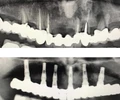

Periimplantitis

Peri-İmplant Mukozitis

Implant tedavisi